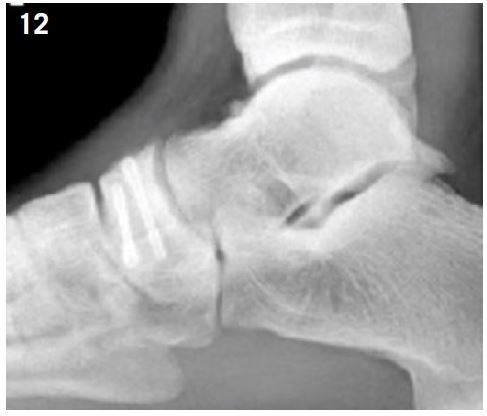

Diagnosis is made by MRI or CT scan (Figure 11).

Screw fixation is recommended in athletes (Figure 12). Return to sports activity can be expected at 4 months post-op35.

Figure 11: Navicular bone fracture visualized by CT Scan.

Figure 12: Navicular bone fracture fixed by double screwing.